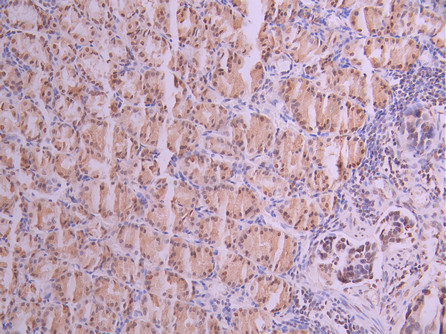

IHC image of CSB-RA168797A0HU diluted at 1:100 and staining in paraffin-embedded human gastric cancer performed on a Leica BondTM system. After dewaxing and hydration, antigen retrieval was mediated by high pressure in a citrate buffer (pH 6.0). Section was blocked with 10% normal goat serum 30min at RT. Then primary antibody (1% BSA) was incubated at 4°C overnight. The primary is detected by a Goat anti-rabbit polymer IgG labeled by HRP and visualized using 0.05% DAB.